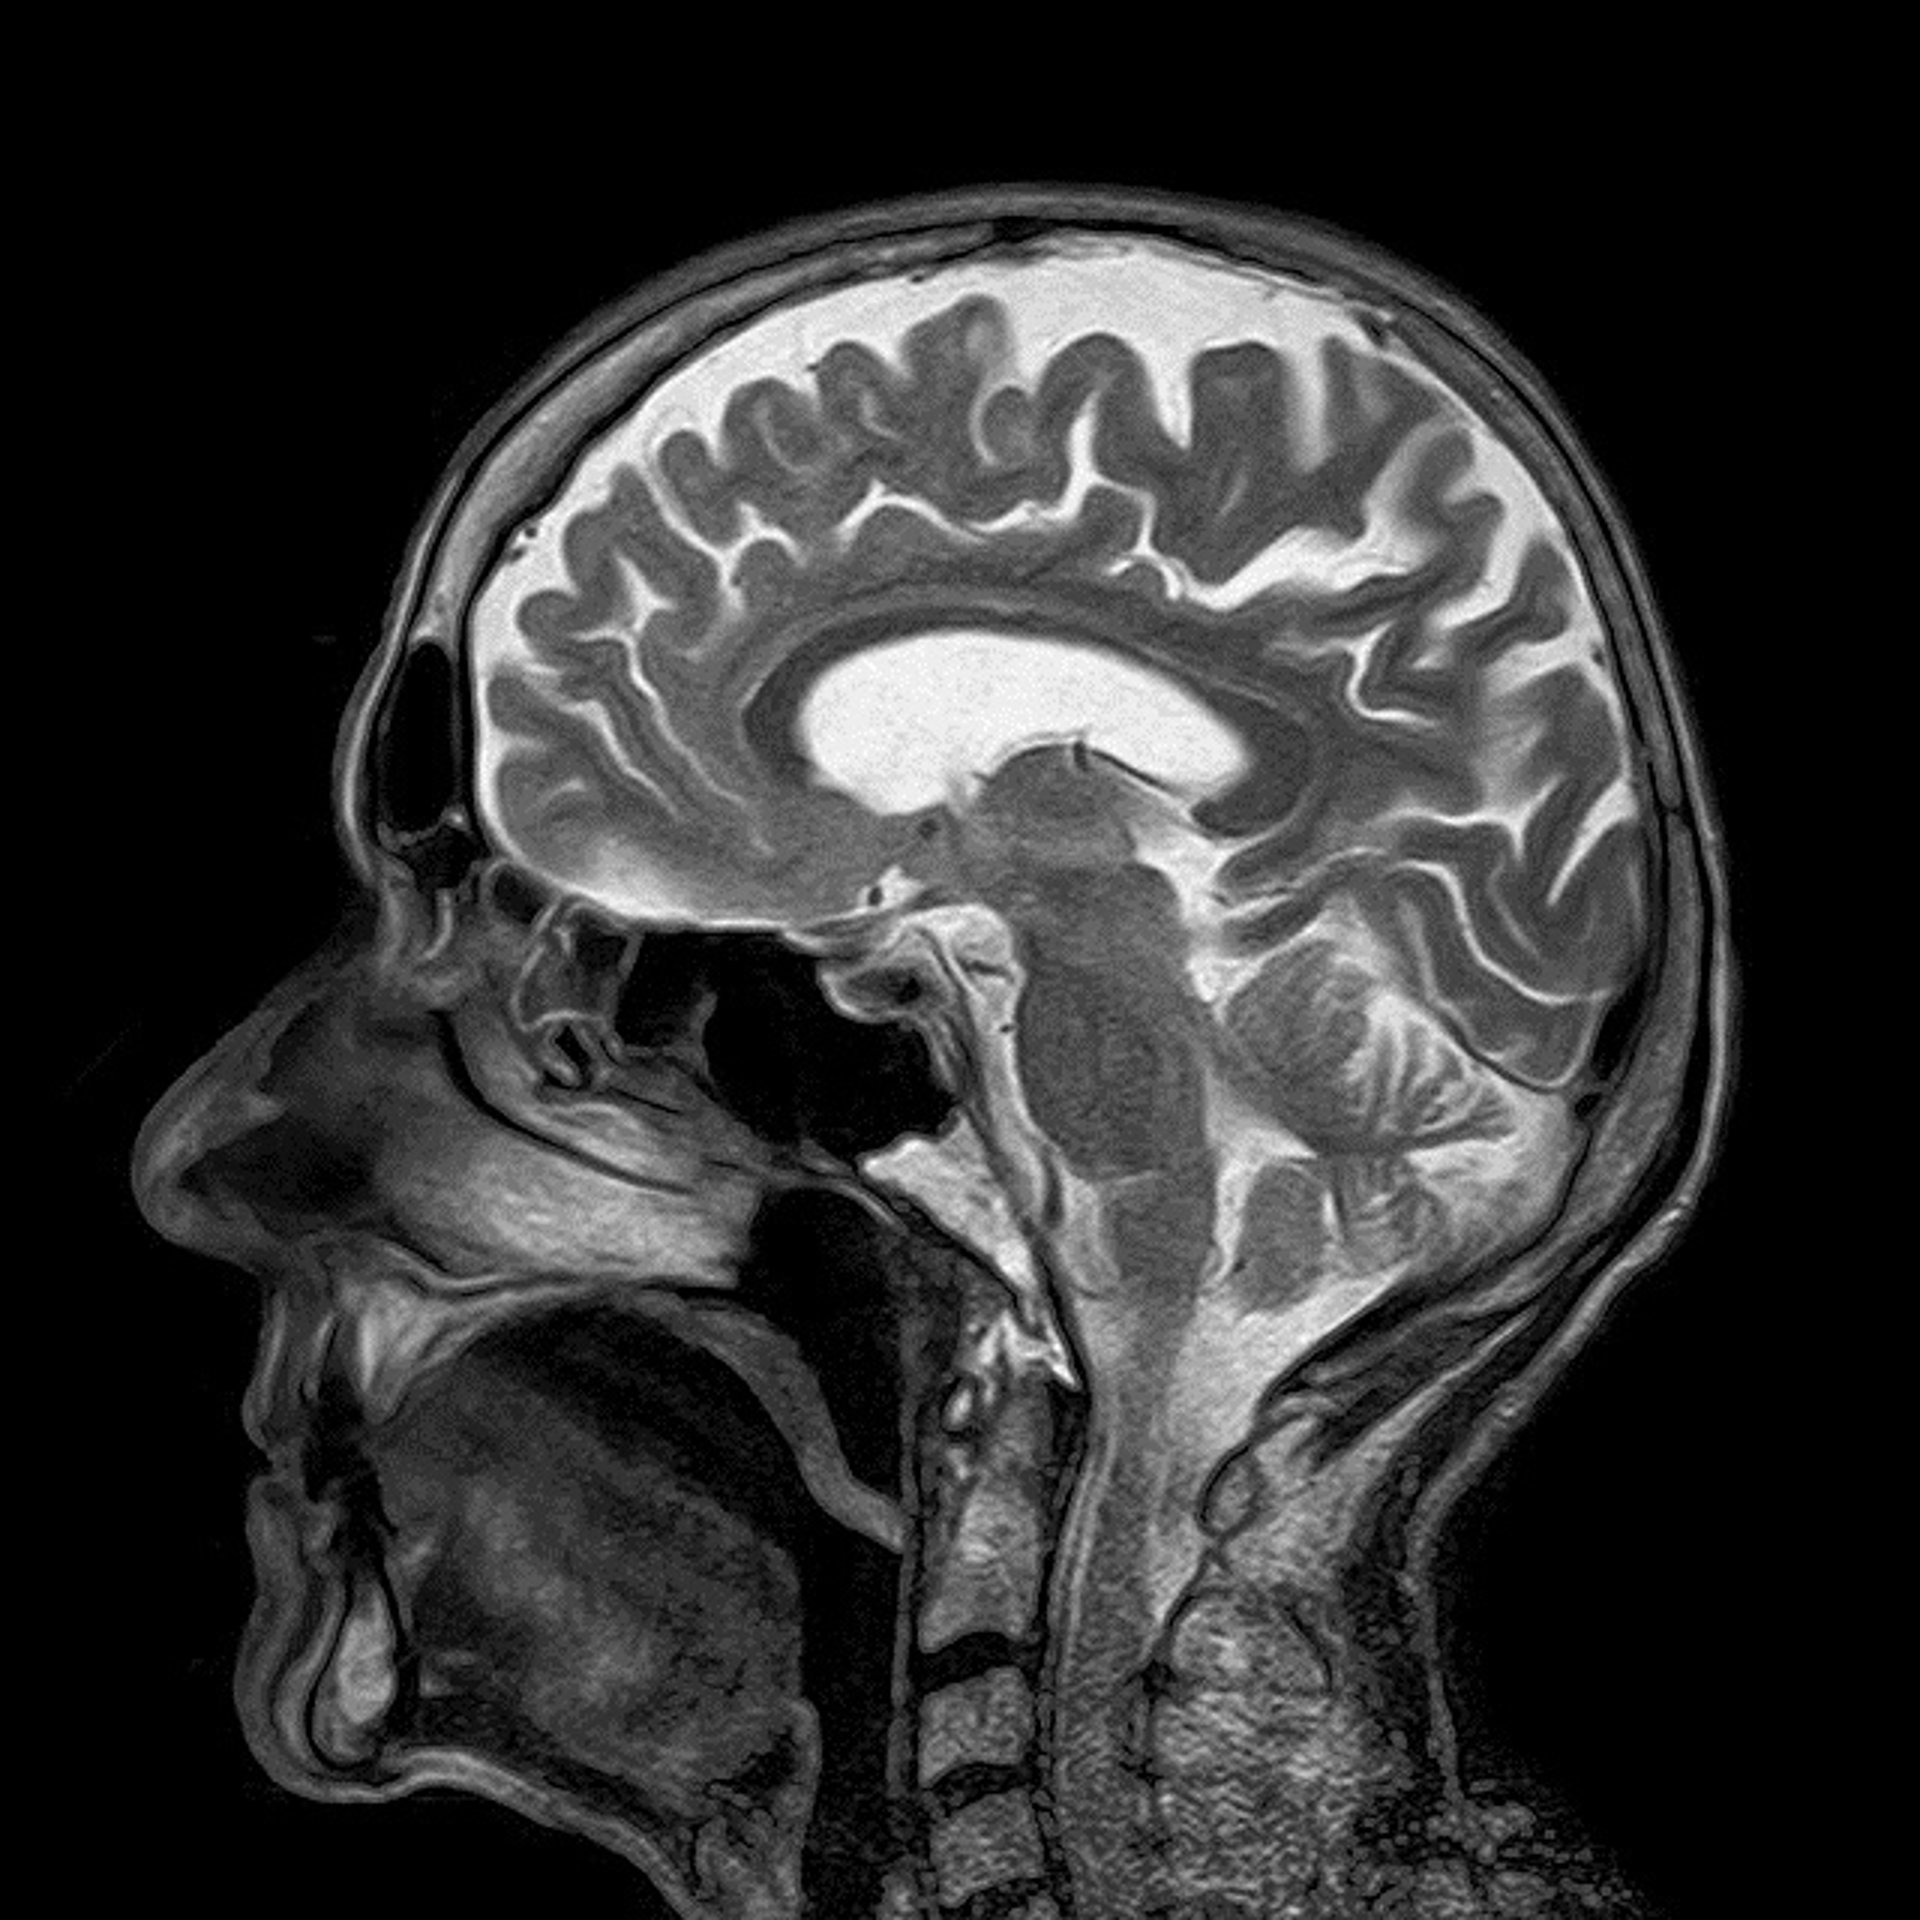

CEREBRO

PIXABAY